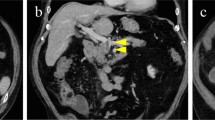

Follow-up duration was ≥ 1 month in 17 patients, < 1 month in 3 patients, and unknown in 57 patients. Outcomes were clearly reported in 64 patients. The rate of improvement of clinical symptoms was 86% (55/64). The mortality was 14% (9/64). Their causes of death included intestinal ischemia/necrosis or perforation (n = 5) and septic shock (n = 4) (Table 2). Univariate logistic regression analyses showed that age (OR = 1.061; 95% CI = 1.011–1.113; p = 0.017), diabetes mellitus (OR = 14.000; 95% CI = 2.544–77.053; p = 0.002), anticoagulant therapy (OR = 0.098; 95% CI = 0.020–0.468; p = 0.004), and bowel resection (OR = 16.000; 95% CI = 2.917–87.766; p = 0.001) were significantly associated with death among SVT patients with COVID-19 (Fig. 3A). Multivariate logistic regression analyses did not identify any independent factor for death among SVT patients with COVID-19.

Risk factors for death among SVT patients with COVID-19 (A) or who received COVID-19 vaccines (B). ALT alanine aminotransferase, AST aspartate aminotransferase, APTT activated partial thromboplastin time, COVID-19 coronavirus disease 2019, CIs confidence intervals, CRP C-reactive protein, CVT cerebrovascular thrombosis, IVIG intravenous immunoglobulin, OR odds ratios, PLT platelet, PT prothrombin time, PE pulmonary embolism, SVT splanchnic vein thrombosis, WBC white blood cell